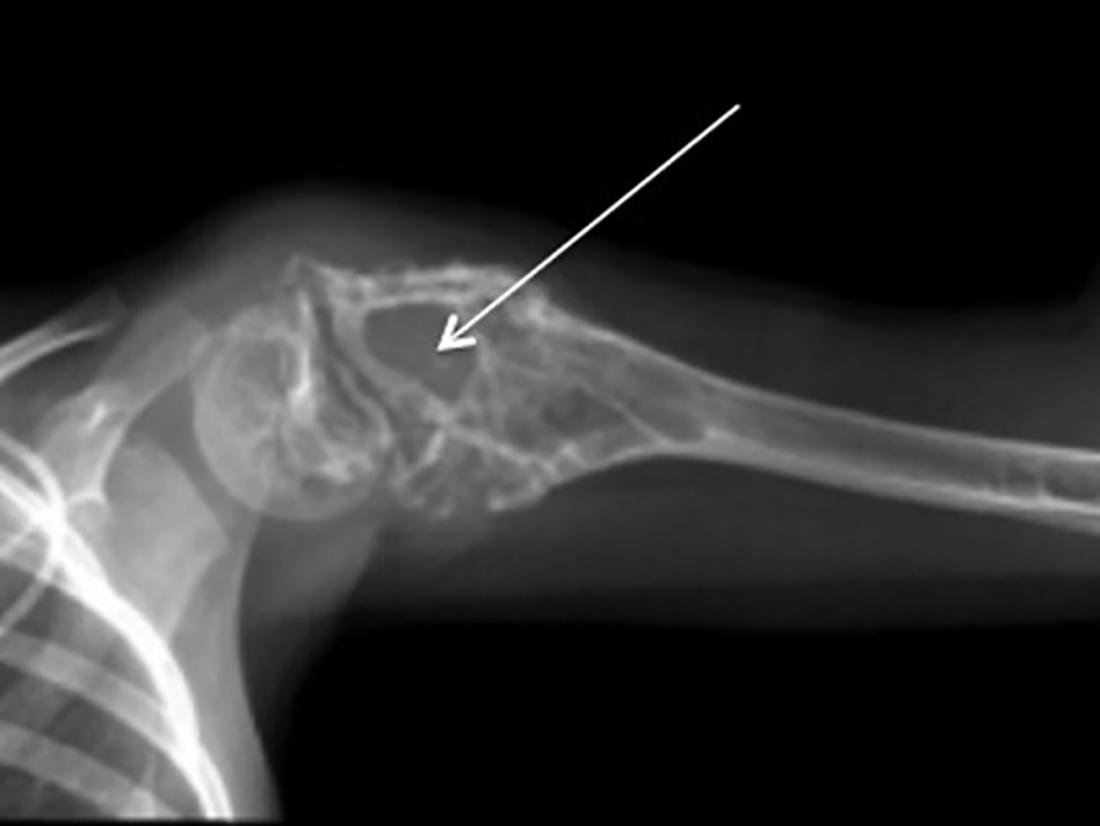

Osteochondroma

Osteochondroma is the most common benign bone tumor, characterized by the growth of a bony projection capped by cartilage. These growths typically occur near the ends of long bones, such as the femur (thigh bone), tibia (shinbone), or humerus (upper arm bone), but can also develop on flat bones like the pelvis or shoulder blades. Osteochondromas develop during childhood or adolescence, often as a result of abnormal bone growth at the growth plate (epiphyseal plate) where bones lengthen. While the exact cause is not fully understood, osteochondromas are thought to arise from a combination of genetic mutations and environmental factors. In many cases, osteochondromas do not cause any symptoms and are discovered accidentally. While osteochondromas are typically benign and do not pose a significant health risk, complications can arise in certain cases.